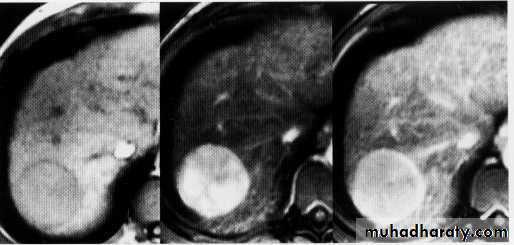

hepatic mets

hepatic mets,arterial phase

hepatic mets venous phase